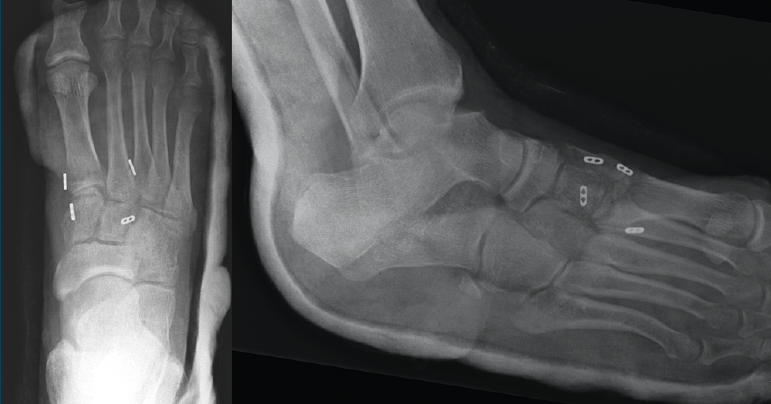

Figura 2. Caso 1. Resultados radiográficos posquirúrgicos.

La revisión a los 3 meses mostró resultados satisfactorios en ambos casos, con tolerancia de la carga completa. Además, las imágenes radiológicas demostraron el mantenimiento de la reducción conseguida en el quirófano, sin movilización del material (Figuras 5 y 6).

Figura 5. Resultados radiográficos posquirúrgicos en el caso 1.

En el primer caso, la incorporación laboral fue a los 4 meses y, en el segundo caso, a los 6 meses; los pacientes no presentaron dolor. A los 10 meses postoperatorios el examen clínico no reveló evidencia de dolor en la zona quirúrgica y los pacientes habían reanudado todas sus actividades regulares, incluida la práctica deportiva, sin complicaciones. Además, las radiografías en ese momento revelaron una reducción anatómica de la lesión.